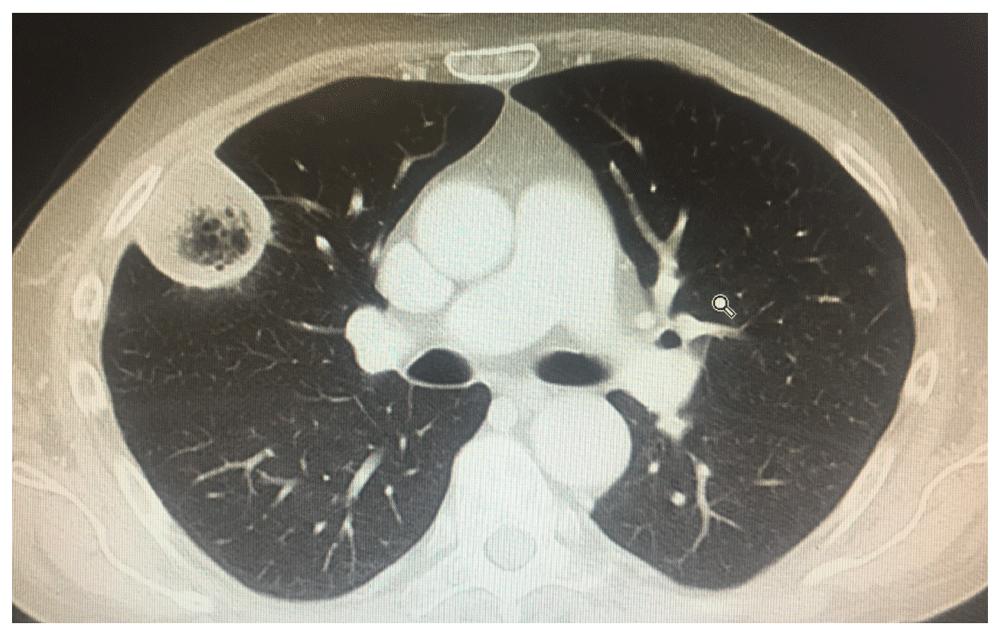

pulmonarymucormycosis

图片尺寸1596x1196

图片尺寸500x336